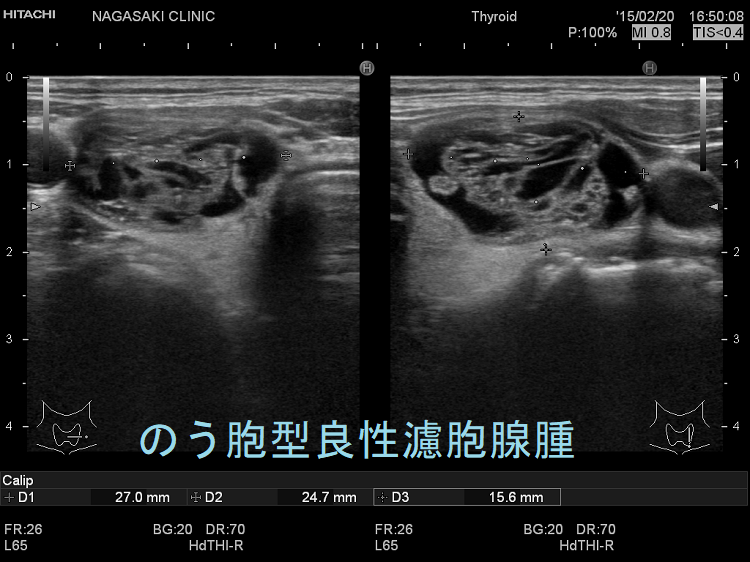

濾胞性甲状腺がんの診断

- 画像検査:医師は、CT スキャンや X 線を使用して甲状腺を詳しく検査することを希望する場合があります。